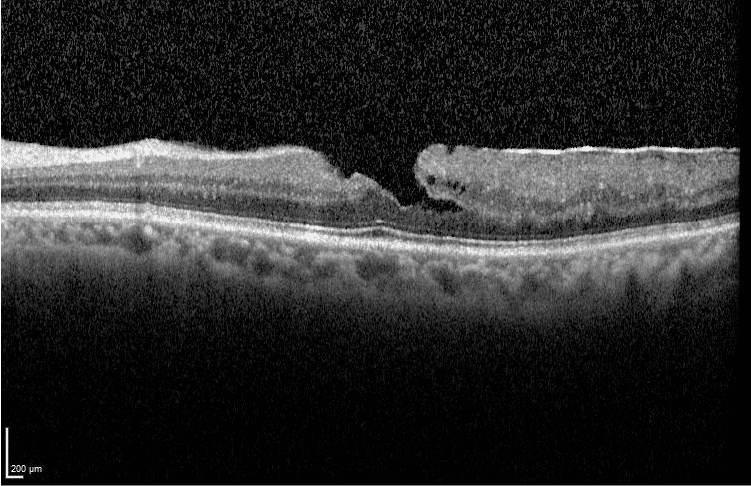

→ Tomografía de Coherencia Óptica u OCT Macular: con esta prueba determinamos el tamaño y la forma del agujero macular para observar el estado de las diferentes capas de la retina y descartar edema macular quístico.

→ Tomografia de coherencia óptica OCT de agujero macular completo.